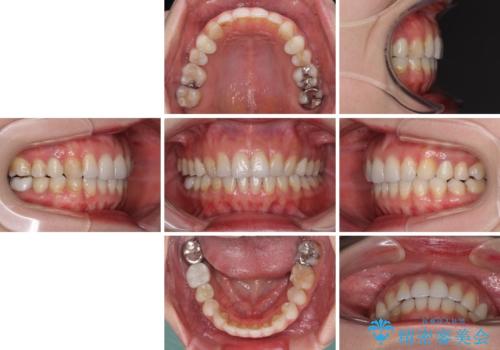

- 失活により変色した歯と不揃いな口元を気にして来院された患者様です。

口元をインビザラインにより歯列を整え、その後に失活している奥歯をオールセラミッククラウンにて補綴治療することとしました。

長時間のマウスピース装着と、患者様自身でのゴムかけに協力いただき、自然な口元に仕上げることができました。

気になっていた変色した歯もオールセラミッククラウンで本物の歯のようになり、患者様には大変満足していただきました。